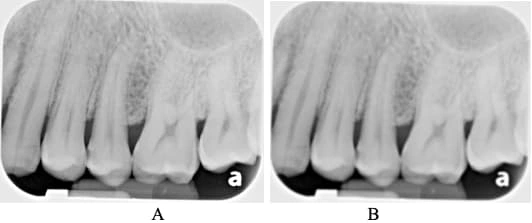

X is for x ray: Image sharpness – Dr. G's Toothpix